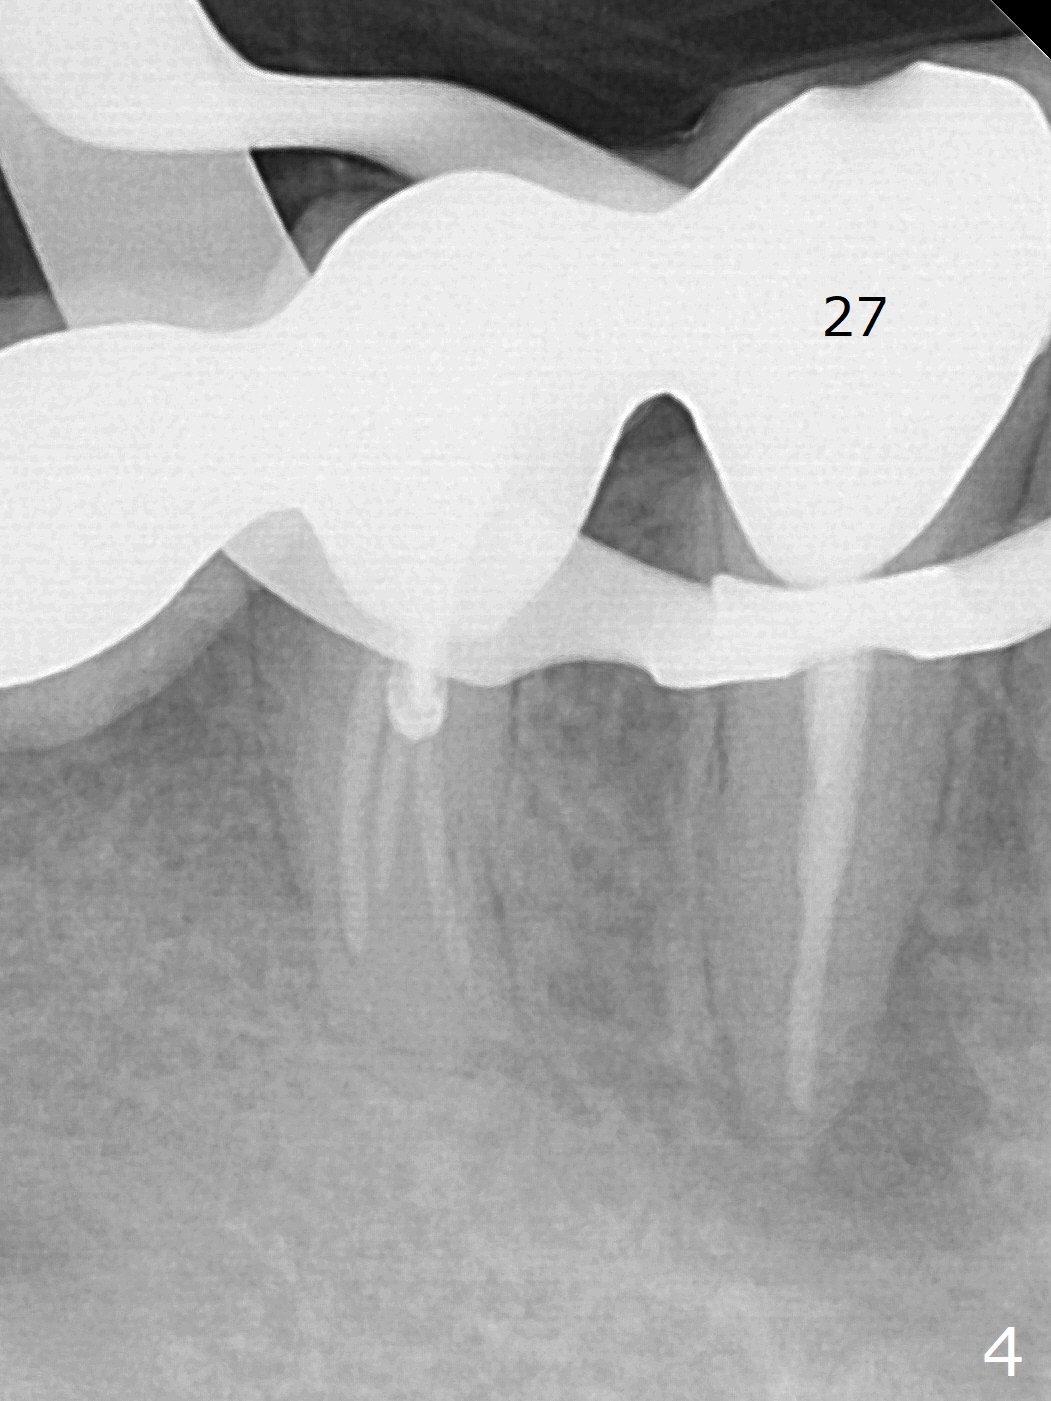

A 66-year-old man has asymptomatic distobuccal (DB) root fracture for ~ 3 years (Fig.1 (>) 2). After #14 implant with limited (M) ortho and 27 and 31 RCT (Fig.3,4), he agrees to have #2 and 3 implants. The tooth #2 has palatal fistula and is tender. Take preop photos. CT should reveal extensive bone loss. Use PRF/sticky bone or GEM21S (if venopuncture is hard) for repair. Save bone from #3 osteotomy for #2 bone graft. Use a special suction with trap after granulation tissue removal.